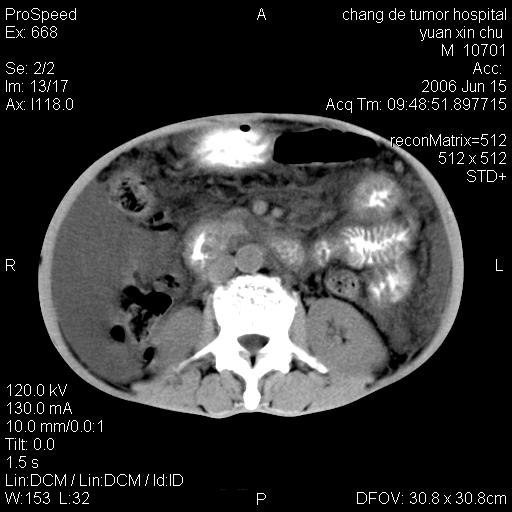

以下是引用qian在2007-4-23 19:06:00的发言:[br]胰腺体积增大,轮廓欠规则,肝轮廓波浪状改变,肝裂增宽,肝周、脾周有液性密度,腹膜后肿大淋巴结,考虑1、胰腺癌伴腹膜后淋巴结转移;2、肝硬化伴腹水。

以下是引用卜一在2007-4-23 20:12:00的发言:[br]胰腺体积增大,轮廓欠规则,肝轮廓波浪状改变,肝裂增宽,肝周、脾周有液性密度,腹膜后肿大淋巴结,考虑1、胰腺癌伴腹膜后淋巴结转移;2、肝硬化伴腹水。支持!